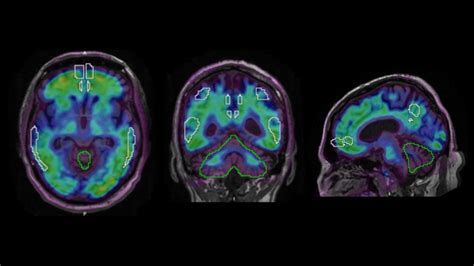

An Amyloid PET scan is a specialized type of medical imaging that uses positron emission tomography (PET) to visualize the density and distribution of beta-amyloid plaques in the brain. Beta-amyloid is a protein fragment that naturally occurs in the body, but in people with Alzheimer’s disease, these fragments clump together to form "plaques." These plaques accumulate between neurons and are believed to disrupt cell-to-cell communication, eventually leading to the cognitive decline associated with dementia.

During the procedure, a radiotracer is injected into the patient's bloodstream. This tracer is designed to bind specifically to amyloid plaques. Once the tracer circulates through the brain, the PET scanner detects the radioactive signal, creating detailed images that allow neurologists to see where these plaques have aggregated.

The decision to utilize an Amyloid PET scan is typically made when the clinical picture is "atypical." For instance, if a younger patient is experiencing rapid cognitive changes, or if symptoms overlap between different types of dementia (such as frontotemporal dementia versus Alzheimer's), this scan can provide the necessary evidence to steer the patient toward the correct treatment path.

The results of an Amyloid PET scan are generally reported as "positive" or "negative." A positive result indicates that a significant amount of amyloid plaque is present, which is consistent with Alzheimer’s pathology. A negative result means that amyloid levels are within the normal range for the patient’s age, which strongly suggests that the cognitive decline is likely caused by something other than Alzheimer’s disease.

Furthermore, new PET tracers are being developed to identify other proteins involved in dementia, such as "tau." While amyloid is a key indicator, tau protein buildup is more closely linked to actual nerve cell death and cognitive symptoms. Having the ability to scan for both markers simultaneously or sequentially will provide an even clearer understanding of a patient’s prognosis and treatment options.